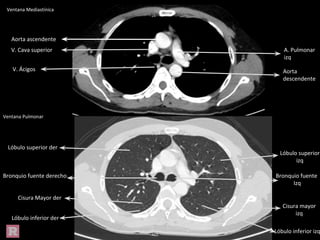

Ventana Mediastínica

Ventana Pulmonar

Aorta ascendente

Aorta

descendente

V. Cava superior A. Pulmonar

izq

V. Ácigos

Bronquio

fuente der

fuente Izq

Cisura

mayor izq

Lóbulo

inferior izq

superior izq

superior der

inferior der

mayor der